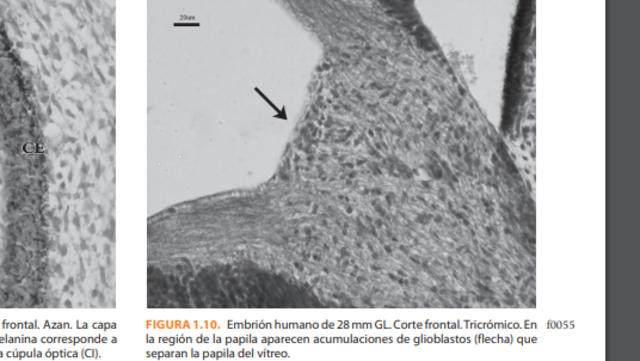

*Se observa el quiasma óptico. En la región de la futura papila aparece una acumulación de glioblastos, esbozo de la membrana limitante de Elschnig y del menisco central de Kuhnt, separando las fibras del nervio óptico del vítreo secundario.